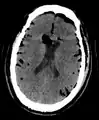

| Pneumocephalus and comminuted fracture of the frontal sinus |

Pneumocephalus is the presence of air or gas within the cranial cavity. It is usually associated with disruption of the skull: after head and facial trauma, tumors of the skull base, after neurosurgery or otorhinolaryngology, and rarely, spontaneously. Pneumocephalus can occur in scuba diving, but is very rare in this context.

If there is a valve mechanism which allows air to enter the skull but prevents it from escaping, a tension pneumocephalus can occur (similar to what can happen in a tension pneumothorax).

CT scans of patients with a tension pneumocephalus typically show air that compresses the frontal lobes of the brain, which results in a tented appearance of the brain in the skull known as the Mount Fuji sign.[1][2][3] The name is derived from the resemblance of the brain to Mount Fuji in Japan, a volcano known for its symmetrical cone. In typical cases, there is a symmetrical depression near the midline (such as the crater of a volcano), due to intact bridging veins.[3] Its occurrence seems to be limited to tension pneumocephalus (not occurring in pneumocephalus without tension).[4] The sign was first described by a team of Japanese neurosurgeons.[5]